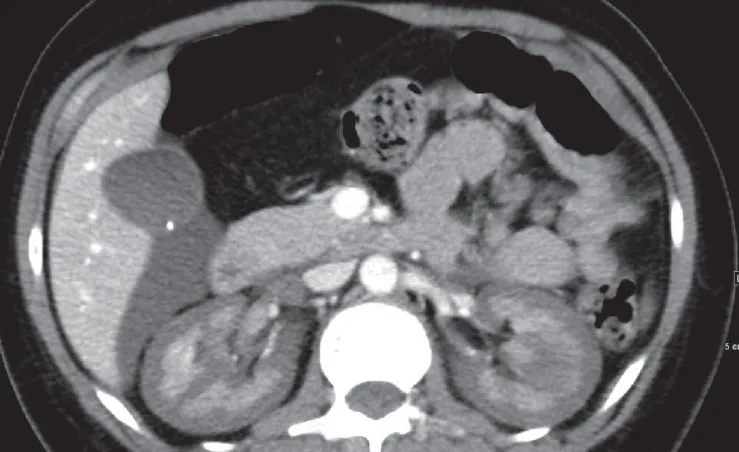

Uma causa incomum de hematúria glomerular intermitente!

Hematúria pós infecção, caso clínicos para auxiliar no entendimento de causas glomerulares comuns e raras...